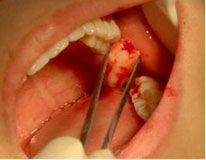

是在患者基本没有痛感的状态下,利用微创拔牙器械拔除患牙。区别于传统拔牙术容易造成拔牙手术创面大、出血多、容易引发干槽症后带来一系列的并发症微创拔牙会给患者带来舒适无痛、愈合快且创面平整不影响后期修复的体验。

麦芽微创拔牙全过程详解点击预约